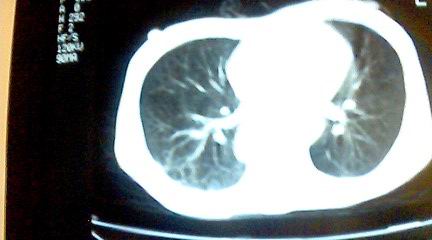

标题: CT25218:请教!胸部CT,胸8椎体骨质破坏,伴周围软组织肿。 [打印本页]

标题: CT25218:请教!胸部CT,胸8椎体骨质破坏,伴周围软组织肿。

患者,女41岁,肢体乏力。

双肺及胸椎结核。

双肺及胸椎结核。支持!

两肺上叶继发性肺结核;胸椎结核并椎旁寒性脓肿形成。